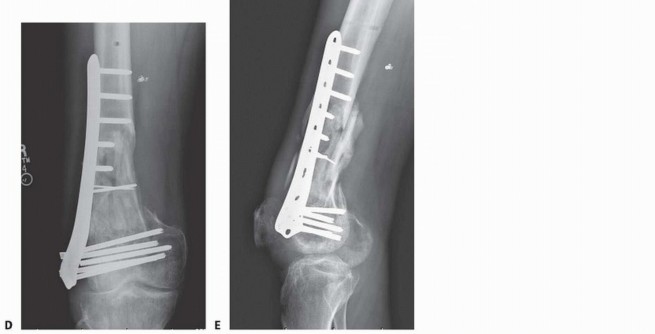

### FIG 9 • Critically ill elderly polytrauma Jehovah's witness patient with left C1 distal femur fracture. A,B. Initial injury AP and lateral views. C,D. Due to extremely low hematocrit, external fixation was the only surgical option allowed to minimize blood loss. Radiographs in bridging external fixation. The AP shows excellent alignment but the lateral shows the expected extension deformity secondary to pull of gastrocsoleus complex. E,F. After 5 weeks in an external fixator, AP and lateral radiographs show callus formation (red arrows). Patient is now cleared for definitive surgical intervention. Antegrade intramedullary nailing has been described and can be used for distal fractures with a large enough distal segment to allow for two locking screws. Malalignment has been a problem, as has adequate fixation. 4, 8 Retrograde intramedullary nailing can be used in the following cases ( FIG 10): All extra-articular type A fractures greater than 4 cm from the joint. This minimal length of the distal femur allows for multiplanar interlocking in the distal fragment. Type C1 or C2 fractures where the articular fracture can be anatomically reduced closed or with limited exposure. Percutaneous screws are used for the articular injury. Periprosthetic fractures around a total knee arthroplasty with an “open box” femoral component Most surgeons prefer to use a long nail, but short supracondylar nails are available as well. Multiple-hole short supracondylar nails have fallen out of favor. Plate fixation ORIF with plates can be used for all types A and C fractures but is ideal for the following injuries: Very distal type A fractures within 4 cm of the knee joint All articular type C fractures, but always for C3 types Periprosthetic fractures about a “closed box” femoral component of a total knee arthroplasty The partial articular type B1 or B2 if an antiglide plate is needed Plate options (preferred to least preferred; fixed-angle devices preferred) Fixed-angle locking plates (percutaneous jigs are advantageous and allow for minimally invasive techniques) Variable-angle (polyaxial) locking plates—allow for “fixed variable locking” within a defined range. It is useful for distal fractures and allows for increased screw 473 trajectories to gain additional locked fixation in short segments, which may not be feasible with fixed-angle trajectory plates ( FIG 11).

### FIG 10 • A,B. AP and lateral radiographs of an elderly patient with multiple comorbidities with an extra-articular distal femur fracture (AO type A; an incomplete intercondylar split— red dashed arrow). C,D. Postoperative radiographs showing stabilization with retrograde intramedullary nail. E,F. One-year postoperative radiographs showing a healed fracture with some subsidence of the metaphyseal region and mild protrusion of hardware through the notch. Ninety-five-degree condylar screw Ninety-five-degree blade plate Nonlocking plates with or without medial support (medial plate or external fixation) Limited internal fixation Limited fixation with screws only can be used for partial articular type B, especially type B3. The amount of open reduction required depends on the adequacy of closed reduction techniques and obtaining an anatomic reduction of the joint surface. Headless screws are useful for type B3 fractures in which the screws have to penetrate the joint surface ( FIG 12). Countersinking the screw heads can also be performed. Biomechanics of fixation: implant considerations There has been concern that the newer locking plate constructs are too stiff, resulting in inconsistent and asymmetric callus formation. 9 Some clinical evidence show less callus formation with stainless steel plates versus titanium plates. 9 Conversely, a biomechanical study has not shown a significant difference mechanically between constructs of stainless steel LISS plates with bicortical screws or titanium LISS plate with unicortical screws.1 474